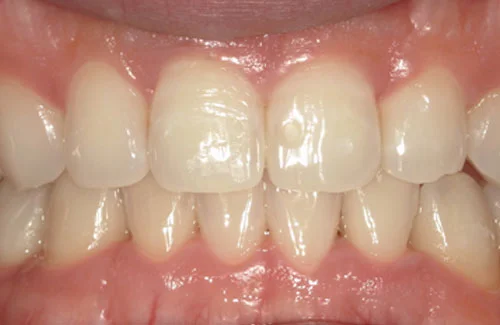

<症例3>前歯のクロスバイトでお悩み

右上の前歯2本が反対に咬合している、いわゆるクロスバイトが主訴でご来院なさいました。

主訴以外の部分には大きな叢生はなく、また患者様も装着時間をしっかり守ってくださったので約6ヶ月で改善することができました。

患者様と症状

主訴:上の前歯が出ている

性別・年齢:20代女性

問題点:上顎左側側切歯のクロスバイト、叢生

診断:前歯部の叢生を伴うアングルⅠ級の不正咬合

主なリスク:矯正中一時的に咬合しにくくなる、歯肉退縮

症状:叢生(そうせい) 上顎前突(じょうがくぜんとつ)

治療内容

治療期間:6ヶ月

治療費用:495,000円(税込)

プラン:14枚コース/ライトプラン

抜歯:親知らずのみ抜歯

再診治療費:無し

追加治療費:無し

保定装置費:無し

治療前後の写真

・2本の前歯が前突しておりましたが、矯正で自然な歯並びになりました。

・前歯の1本が下の歯の裏側に噛み合うクロスバイトになっていましたが、矯正で改善されました。